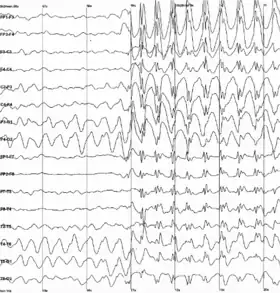

As a side effect of the electrochemical processes used by neurons for signaling, brain tissue generates electric fields when it is active. When large numbers of neurons show synchronized activity, the electric fields that they generate can be large enough to detect outside the skull, using electroencephalography (EEG)[73] or magnetoencephalography (MEG). EEG recordings, along with recordings made from electrodes implanted inside the brains of animals such as rats, show that the brain of a living animal is constantly active, even during sleep.[74] Each part of the brain shows a mixture of rhythmic and nonrhythmic activity, which may vary according to behavioral state. In mammals, the cerebral cortex tends to show large slow delta waves during sleep, faster alpha waves when the animal is awake but inattentive, and chaotic-looking irregular activity when the animal is actively engaged in a task, called beta and gamma waves. During an epileptic seizure, the brain's inhibitory control mechanisms fail to function and electrical activity rises to pathological levels, producing EEG traces that show large wave and spike patterns not seen in a healthy brain. Relating these population-level patterns to the computational functions of individual neurons is a major focus of current research in neurophysiology.[74]

Neurophysiologists study the chemical, pharmacological, and electrical properties of the brain: their primary tools are drugs and recording devices. Thousands of experimentally developed drugs affect the nervous system, some in highly specific ways. Recordings of brain activity can be made using electrodes, either glued to the scalp as in EEG studies, or implanted inside the brains of animals for extracellular recordings, which can detect action potentials generated by individual neurons.[113] Because the brain does not contain pain receptors, it is possible using these techniques to record brain activity from animals that are awake and behaving without causing distress. The same techniques have occasionally been used to study brain activity in human patients with intractable epilepsy, in cases where there was a medical necessity to implant electrodes to localize the brain area responsible for epileptic seizures.[114] Functional imaging techniques such as fMRI are also used to study brain activity; these techniques have mainly been used with human subjects, because they require a conscious subject to remain motionless for long periods of time, but they have the great advantage of being noninvasive.[115]